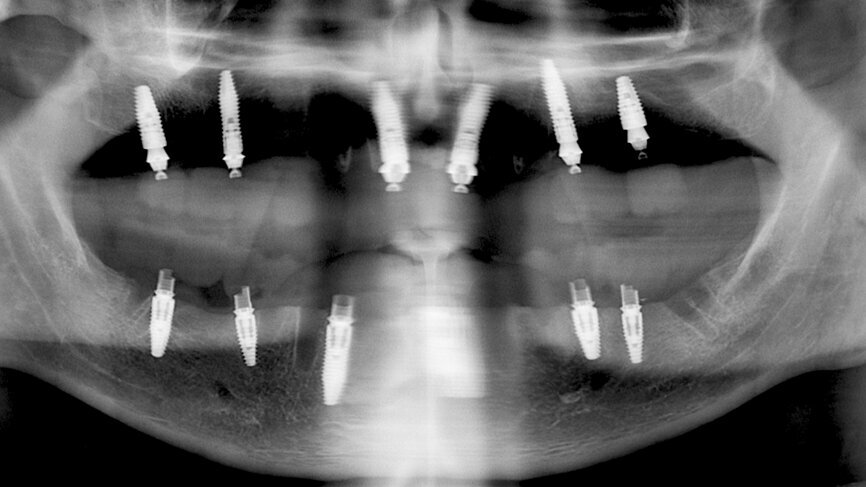

Returning to the patient, the healing caps were removed (Fig. 19), and the prosthesis was placed, allowing for a passive fit on the abutments, with an initial handpiece tightening of each SRA screw to 5 N cm. After the seating was checked, the torque of each SRA screw was increased, also with the handpiece, to 35 N cm (Fig. 20). The occlusion was checked and contacts were inspected (Fig. 21). The screw holes were sealed with PTFE and a temporary filling material. A panoramic X-ray was taken, and SRA screw positions were evaluated to confirm the perfect temporary bridge fit (Fig. 22). The patient was discharged on 500 mg of amoxicillin every 8 hours and 25 mg of dexketoprofen every 12 hours for one week. Oral hygiene and diet instructions were given, and a one-week follow-up appointment was scheduled.